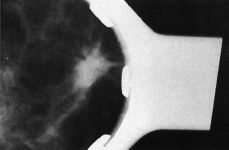

Mama Utilización de los criterios de la cicatriz radial en el diagnóstico diferencial de las lesiones estrelladas de la mama

Breast Utilization of radial scar criteria in the differential diagnosis of stellate breast lesions